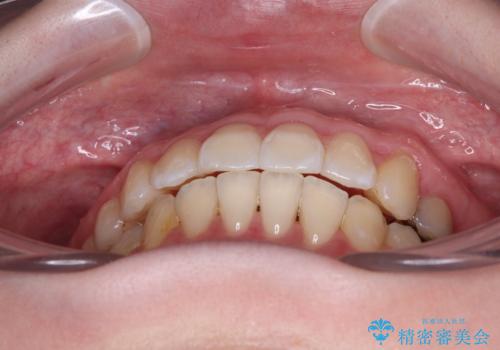

開咬と前方に飛び出した前歯 インビザラインによる矯正治療

- 上下前歯の非接触と叢生を気にして来院された患者様です。

開咬の改善はインビザラインの最も得意とするところであるため、インビザラインを用いて矯正治療を行うこととしました。

舌の突出癖改善のトレーニングをしっかりと行っていただき、上下前歯が接触する咬み合わせを達成することができました。